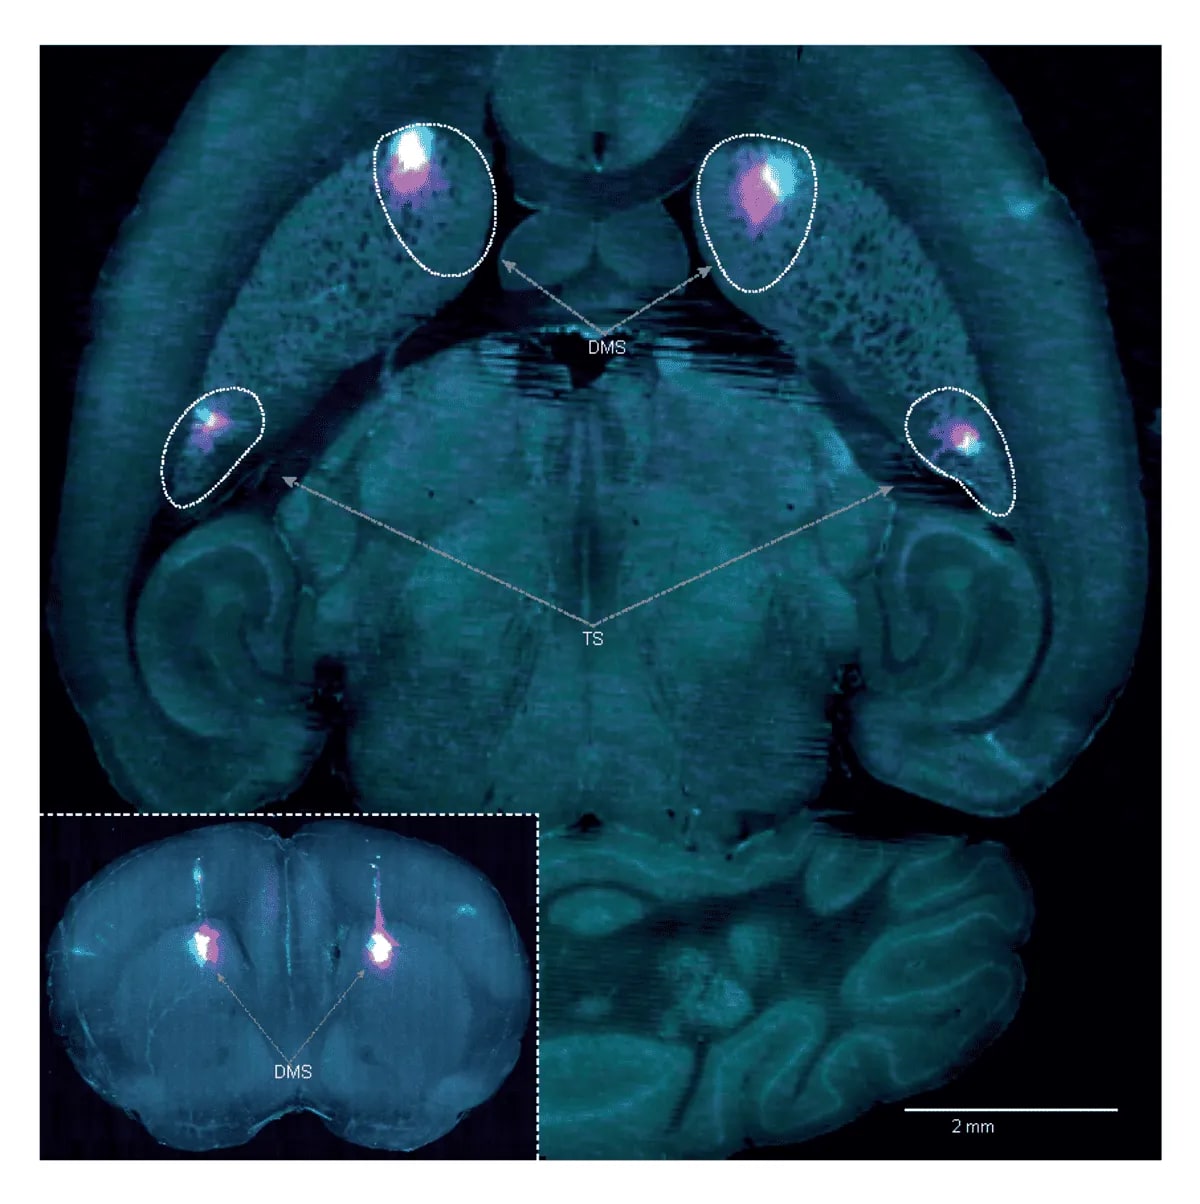

Secciones del cerebro con regiones DMS y TS resaltadas con fluorescencia

Imágenes cerebrales que muestran las regiones inactivadas durante una tarea conductual: el cuerpo estriado dorsomedial (DMS) y la cola del cuerpo estriado (TS). Crédito: Hernando Martínez Vergara.

Los investigadores usaron sensores de dopamina en ratones y pruebas de discriminación auditiva para demostrar que las neuronas de la cola del cuerpo estriado liberan dopamina relacionada con el movimiento, no con recompensas. Al dañar esta región, observaron que los ratones no desarrollaban preferencias automáticas, manteniéndose en un aprendizaje lento y dependiente del sistema basado en valores.

Esto sugiere que el sistema APE es fundamental para formar hábitos estables, mientras que el sistema RPE actúa durante las etapas iniciales del aprendizaje. Cuando los investigadores silenciaron la cola del estriado en ratones expertos, su rendimiento se desplomó, lo que confirmó la dependencia del sistema habitual en fases avanzadas del aprendizaje.